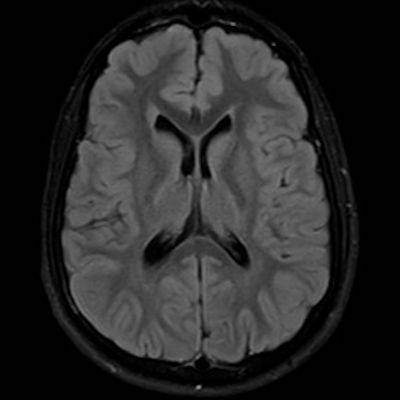

11 ay, Nöbet

Charlevoix-Saguenay Otozomal Resesif Spastik Ataksisi (ARSACS)

ARSACS (Charlevoix-Saguenay otozomal resesif spastik ataksisi) Sendromu